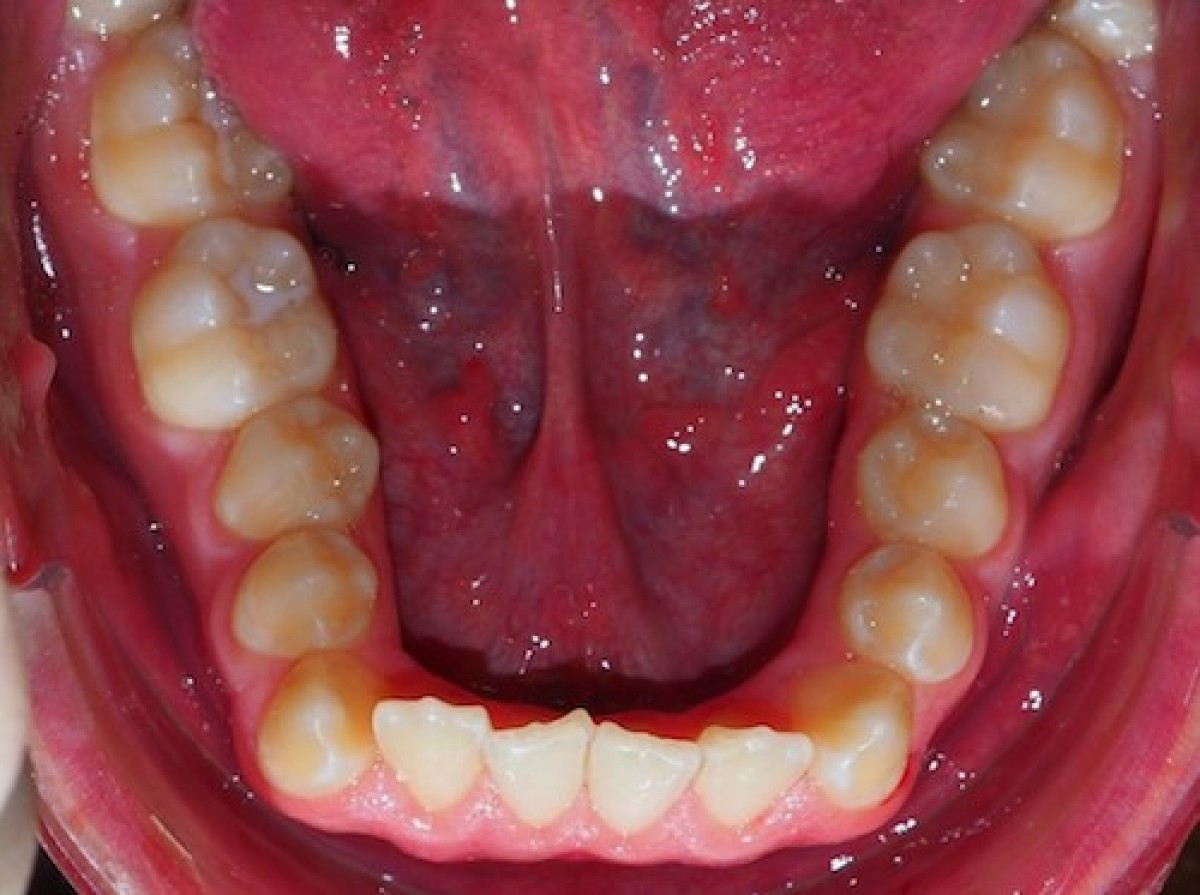

In the pictures below, a proper shape of the archwire was selected, so intermolar and intercanine width did not change during treatment and no roundtrip movement occurred, even using a NiTi archwire. Archwire selection had been made on virtual models (Insignia Approver, Ormco). A survey by McNamara et al. (McNamara C, Drage KJ, Sandy JR, Ireland AJ. An evaluation of clinicians’ choices when selecting archwires. Eur J Orthod. 2010;32:54–59.) revealed significant variation in archwire selection methods among orthodontists. Most orthodontists selected archwires subjectively by visual assessment of the adaptation of the archwires to the facial axis or facial surface of the teeth, incisal edges and cusp tips, or the facial portion of the proximal contacts. McNamara et al. then raised a question regarding the possibility of using digital models for accurate archwire selection, as Computer software could act as a decision support system to increase agreement in treatment results.